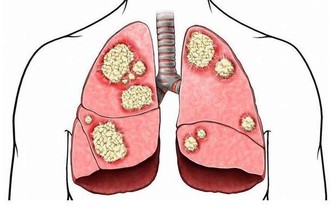

目前中國有1億人左右患有靜脈曲張,靜脈曲張的問題不僅僅是看上去不雅觀,更重要的是,當靜脈曲張累積到深靜脈時,或引起肺栓塞,導致猝死。

以上方法的核心思想就是收縮小腿肌肉,促進血液回流,如果你有其餘的辦法也能達到這種效果,也可以一試。在這裡,主要是給年輕人們提個醒,如果你現在就發現自己有靜脈曲張,一定要加以重視,及時干預,將肺栓塞的可能性降到最低。